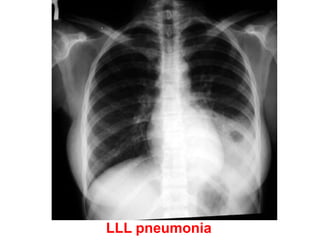

RLL pneumonia

LLL pneumonia

Left Lower Lobe Pneumonia

26